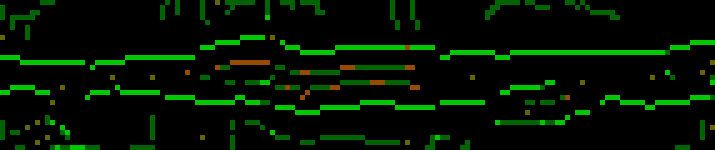

6, 7. Чтобы построить границы воспользуемся поиском пути. В качестве начальной и конечной берутся ближайшие крайние точки с наименьшей стоимостью. Для поиска пути используется обычный поиск в ширину, который выбирает граничные точки с наименьшей стоимостью. Также доступны прыжки, но цена их высока. Верхняя и нижняя границы сосуда ищутся раздельно, и после к ним применяется сглаживание:

Такая процедура выполняется для каждой плоскости, что в результате дает шестнадцатисегментные кольца для каждого среза в стопке. Эти кольца формируют внешние границы сосуда.

Как видно из изображения, есть участки, в которых границы обнаружены неправильно. Это происходит из-за наличия кальция, что в результате приводит к обнаружению границ кальция, а не границ сосуда. Чтобы такого не происходило после первого обнаружения границ необходимо определить порог кальция (об этом дальше), а затем выполнить второе обнаружение границ, игнорируя воксели, относящиеся к кальцию. Тогда получим: